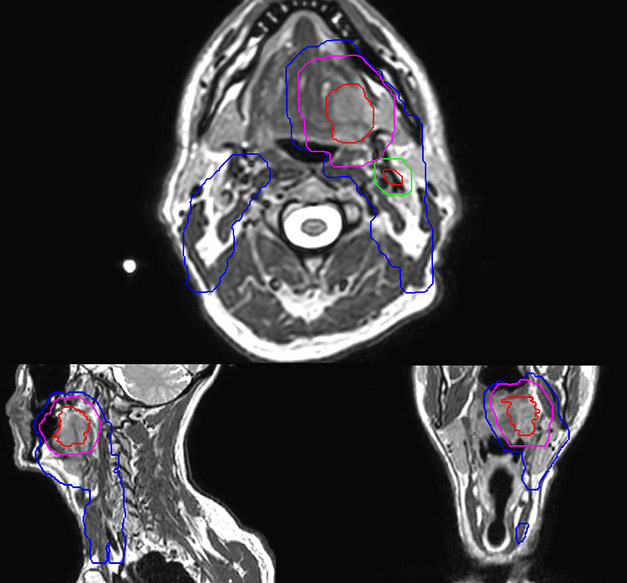

Epidermoid carcinoma of the left tongue base

The patient was diagnosed with an epidermoid carcinoma of the base of the left invading the amygdala lodge and the amygdaloglossal groove. Radiochemotherapy with curative aim was prescribed with a dose of 70 Gy for the tumor, 66 Gy on the suspicious nodes and 56 Gy on the elective drainage areas - in 33 fractions.

MR-based target contouring on 3D T2W TSE in transversal, sagittal and coronal planes.

Personalized VMAT dose planned in Philips Pinnacle.